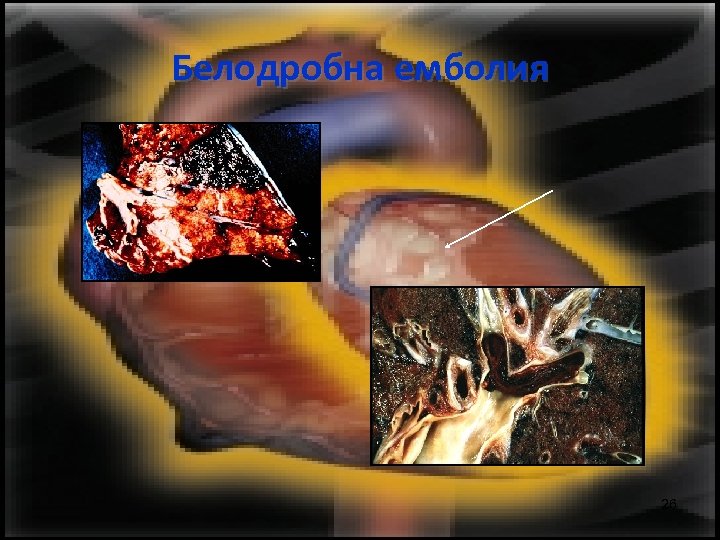

Белодробна емболия 26

Белодробна емболия 22